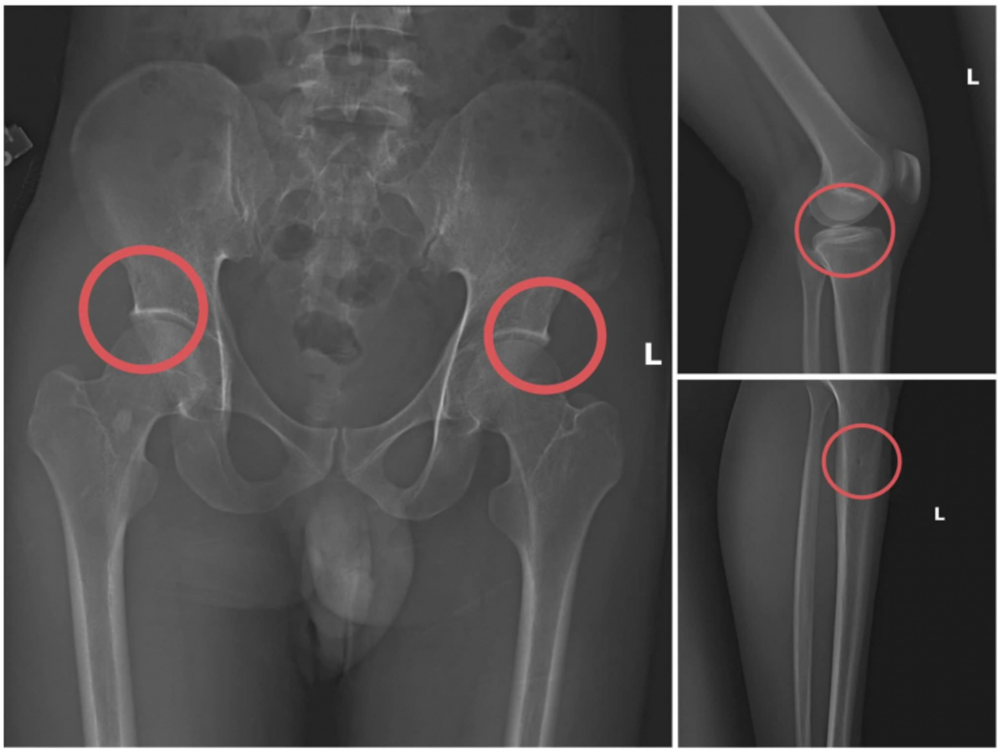

Đáng chú ý, Châu trực tiếp tiêm thuốc mê và dùng kim tiêm cùng búa tác động vào vùng xương của người mua bảo hiểm, tạo ra các vết nứt vỡ giống hệt thương tích do tai nạn. Sau khi gây thương tích, Châu hướng dẫn các đối tượng dựng hiện trường giả như điện giật ngã hay trượt chân xuống suối để hợp thức hóa bệnh án và hoàn chỉnh hồ sơ yêu cầu chi trả bảo hiểm.